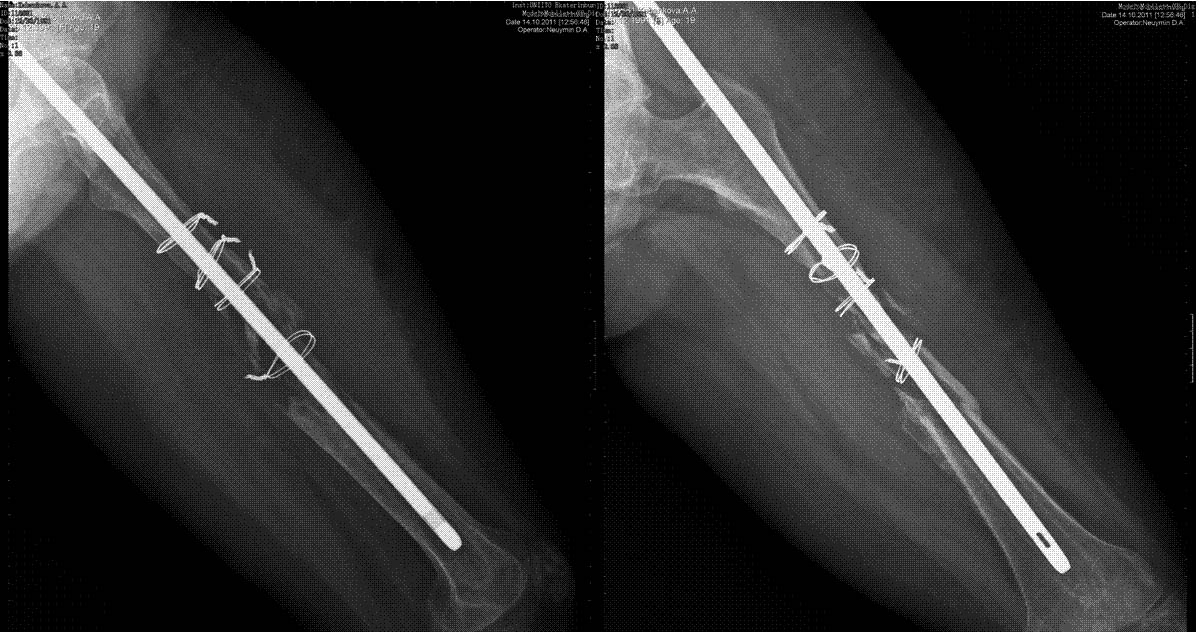

дефект бедренной кости при интрамедуллярном остеосинтезе

Уважаемые коллеги, выскажите пожалуйста свое мнение.пациентка 19 лет. выполнен остеосинтез стержнем,

в послеоперационном периоде лизирование кости между проволочными петлями. у пациентки укорочение бедра 3,4см.+ дефект 10см.

Да и укорочение выглядит куда больше чем 3-4 см

Уважаемый Александр, конечно очень мало информации, но исходя из снимков, лизис кости возможно связан с фиброзной дисплазией или опухолью,если конечно вы исключили инфекцию, хотя на снимках не видно воспаления мягких тканей.

репозиция небось открытая была и кость небось ободрали изрядно при этом? + серкляжи = результат налицо.

Гипотрофический ложный сустав (возможно инфицированный) и нестабильность имплантата. Он мигрирует кверху.

Вариант выбора- БИОС с АБ покрытием и костной аутопластикой.

Извиняюсь, за малое количество информации, исправлюсь. травма от июля 2009 года, синтез выполнен через неделю.

предоперационные снимки и сразу после синтеза очень плохого качества, но дефекта между серкляжами нет. не считая серкляжей репозиция выполнена удовлетворительно. воспалительных явлений в послеоперационном периоде не было, пациентка ходит на костылях не нагружая конечность. ортопедическое укорочение действительно 3 см., выстояние стержня из точки входа сразу после операции выявлено.

интересно было бы услышать мнения о возможных причинах лизиса, склоняемся к версии о сдавлении серкляжными петлями, что на фоне отсутствия нагрузки дало отрицательный результат.